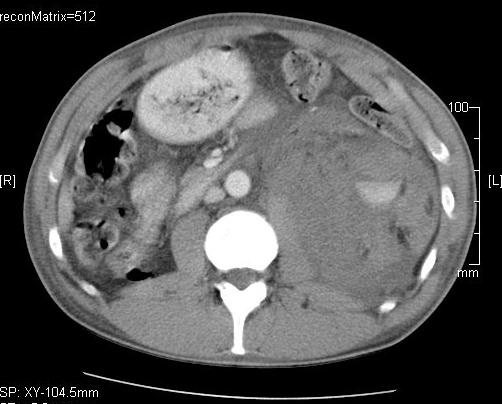

- Hemorrhage (subcapsular (figure 12.), parenchymal, intraabdominal (figure 13.), intrathoracic, pseudoaneurysm),

Image

Figure 13. – US guided renal biopsy, serious retroperitoneal and intraabdominal hemorrhage, with active bleeding (20 hour control)